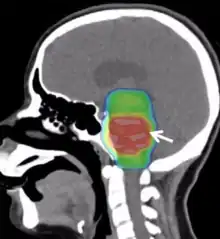

| Diffuse intrinsic pontine glioma | |

| Magnetic resonance imaging of a diffuse intrinsic pontine glioma. | |